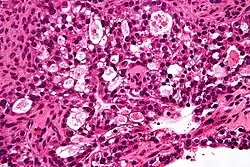

Mucinous tumors include mucinous adenocarcinoma and mucinous cystadenocarcinoma.[29]

Mucinous adenocarcinoma

Mucinous adenocarcinomas make up 5–10% of epithelial ovarian cancers. Histologically, they are similar to intestinal or cervical adenocarcinomas and are often actually metastases of appendiceal or colon cancers. Advanced mucinous adenocarcinomas have a poor prognosis, generally worse than serous tumors, and are often resistant to platinum chemotherapy, though they are rare.[29]